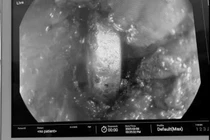

Trong lúc biểu diễn xiếc, khi nuốt được một nửa thanh kiếm dài hơn 40cm, anh T. cảm thấy đau và không thể tiếp tục nhấn vào sâu nữa, nên lập tức rút kiếm ra và nhanh chóng đến bệnh viện.